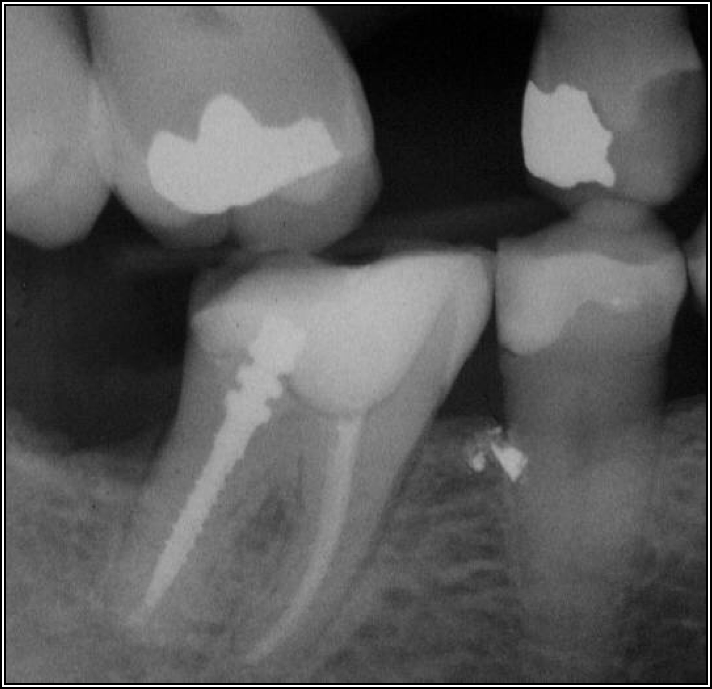

If a tooth stands alone, greater forces will be placed on it because it has no adjacent teeth to provide support. This situation will affect the decision-making process for placing a post. Figure 3 shows a tooth that was on an island and would be having three implants placed in front of it. The tooth would take a much greater beating than another tooth that had support proximally. Even though it had a good root canal, the clinician would need to account for whether the tooth would last until the implants integrated. Figure 4 shows a case that would quickly proceed to implants. The patient had a less-than-ideal bridge for over a decade, with decent endodontics and functionality. There was also an overhang on the premolar. The post was not ideal in this case because there was one distal canal and not all the gutta-percha was removed from it. An intimate fit should be the goal with the post and the walls. Whether using a threaded or non-threaded post, there should not be excess gutta-percha because it is not as solid as the tooth and will lead to greater movement. That movement on the tooth and bridge will create too much force and result in demise.

Fig 4. Case that quickly would proceed to implants.

Figure 4